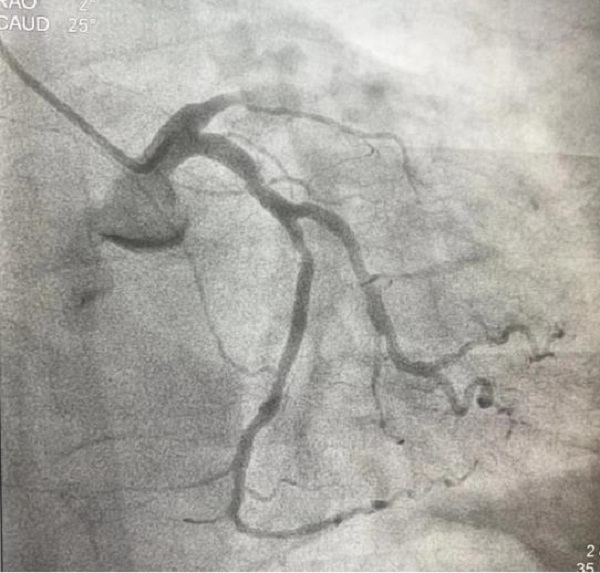

时间紧迫,容不得丝毫犹豫,刘积伦主任团队在告知患者家属相关病情后,立即为患者进行了紧急冠脉造影及支架植入术。手术中,医护人员每一个动作都精准而果断,很快,闭塞的血管被成功开通,恢复3级血流,王先生的心脏重新焕发了生机。